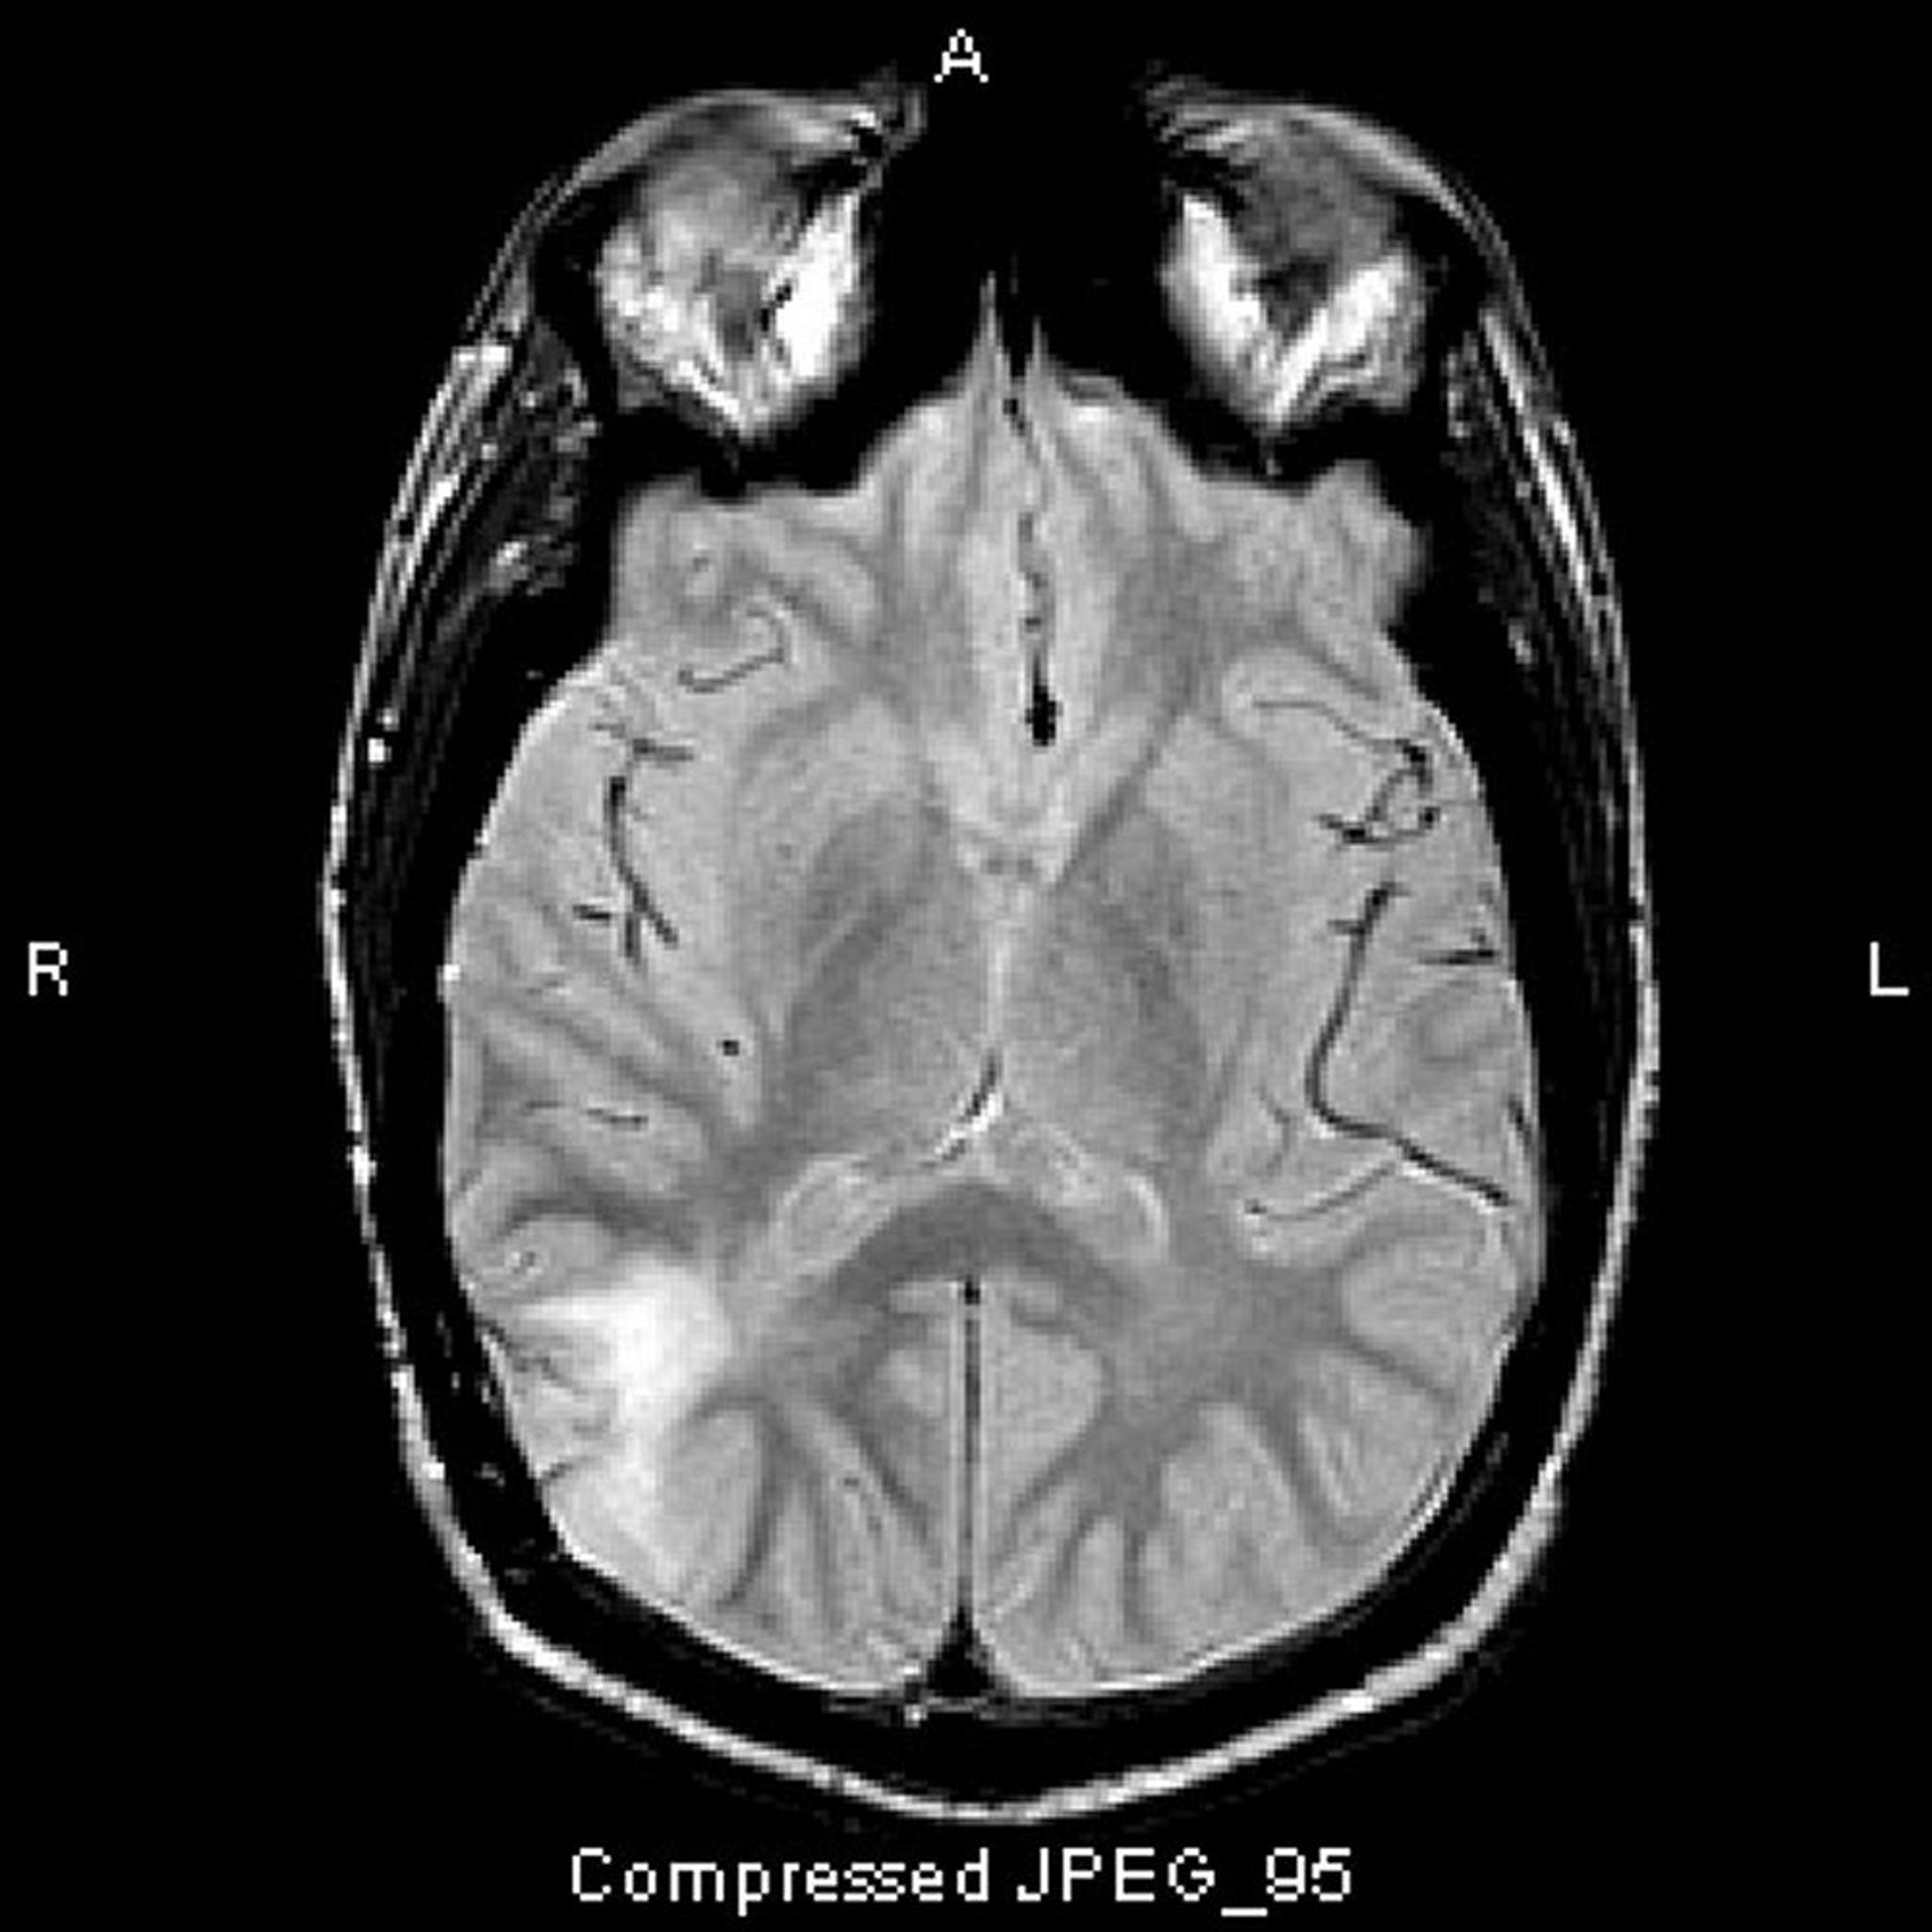

Dieser T2-FLAIR-MRT-Scan zeigt ein weißes Signal im hinteren Temporallappen. Das Signal wird nicht durch Kontrastmittel verstärkt. Es handelt sich um ein anaplastisches Astrozytom (Grad III).

Image courtesy of William R. Shapiro, MD.